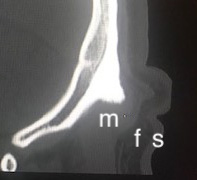

Occipital Skull Knob Anatomy Dr Barry Eppley Indianapolis